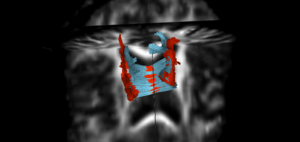

For a longitudinal evaluation, its necessary to have all the DTI scans co-registered. Using the QCed versions, we co-registered the acute and chronic timepoints using the corresponding FA images, with the chronic FA image as our moving image. We also applied masks to improve the registration accuracy. The obtained affine + spline transform was applied to the DTI image along with tensor-appropriate resampling. Following the co-registration, a common ROI was created for the middle portion of the corpus callosum tract which for the given patient, seems to be in the region not directly in the proximity of the lesions. The fibers from the chronic timepoint seems to have undergone some geometry changes as well as the associated diffusion profiles indicate a loss of white matter integrity over time.